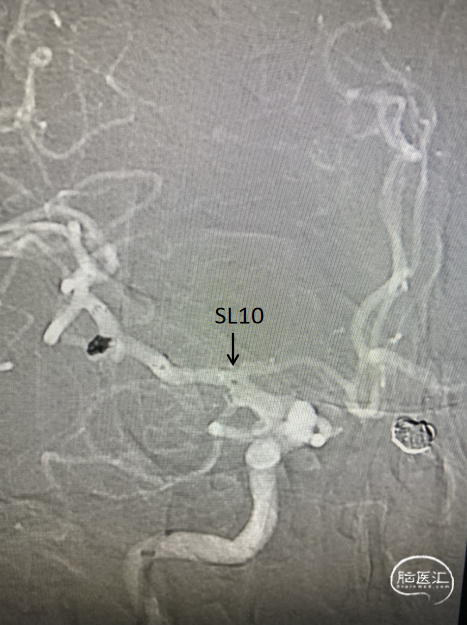

术中三维所见

6F导引导管至于左侧C2段,在Synchro-0.014 200cm微导丝携带下将PROWLER SELECT PLUS微导管送至左侧大脑中动脉M2段,在ASAHI CHIKAI-0.014 200mm微导丝携带下将Echelon 10微导管送至瘤腔内。

路图引导下将4mm×12cm 3D弹簧圈(EV3)沿微导管置入动脉瘤腔内暂不解脱,沿支架微导管将4.5mmx22mm支架(Enterprise)置入左侧颈内动脉交通段。继续填入弹簧圈